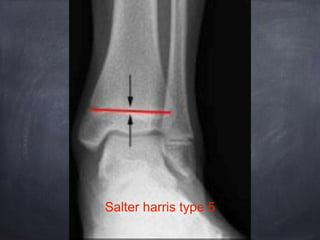

Salter harris classification

Salter harris type 5